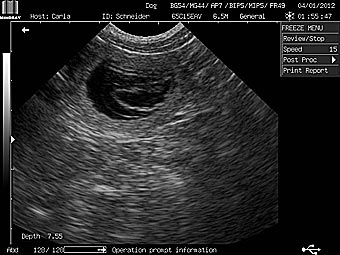

Am 3. Januar erhielten wir den Beweis: Carla ist tragend! |